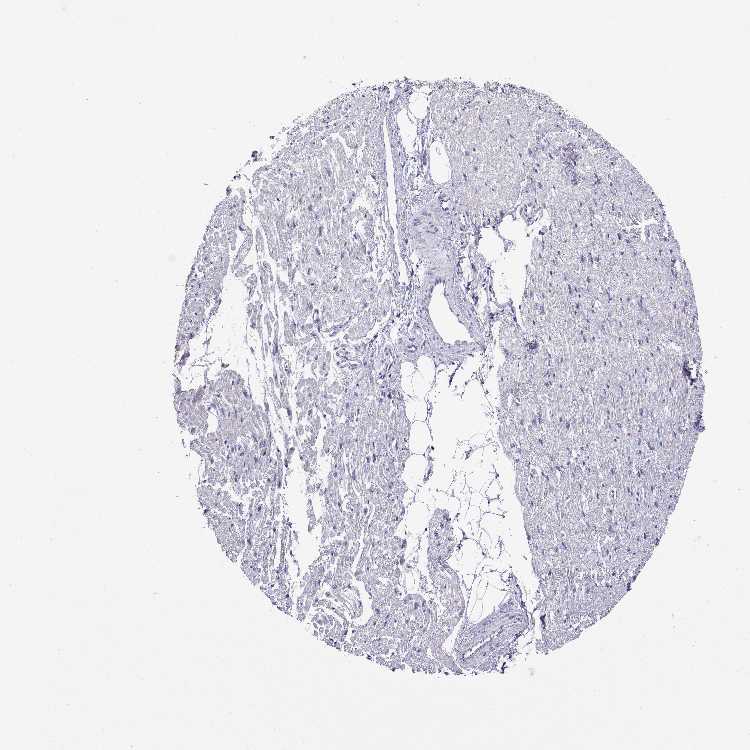

HEART MUSCLE - Antibody stainingi

Antibody staining in the annotated cell types in the current human tissue is reported as not detected, low, medium, or high, based on conventional immunohistochemistry profiling in selected tissues. This score is based on the combination of the staining intensity and fraction of stained cells.

Each image is clickable and will lead to virtual microscopy that enables deeper exploration of all samples and also displays staining intensity scores, fraction scores and subcellular localization as well as patient and tissue information for each sample.

Antibody HPA065235

Cardiomyocytes Not detected